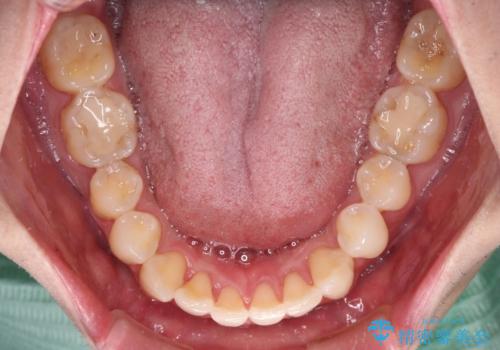

ディープバイトと叢生 インビザラインによる矯正治療

上下ともに叢生が認められたため、親知らずすべてを抜歯し、歯列全体を後方へ移動させることで歯列を整えることとしました。

ディープバイトもデコボコも改善され、気になっていた銀歯もセラミックとなり、患者様には大変満足していただきました。